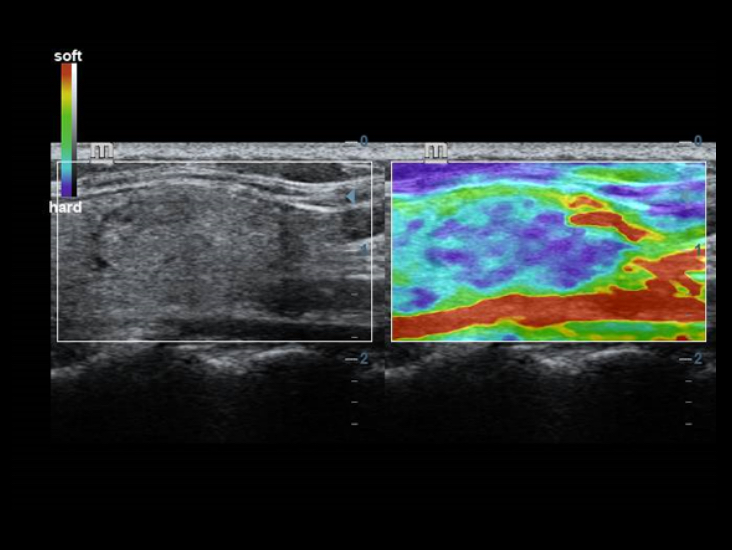

???? ?? ??: ??? ?? ?? ??

?? ??? ????? ??????? ???? ?? ??? ?????? Full HD ??? ?? DC-40? ?? ?? ??? ??? ??????.

- iClear(??? ?? ?? ??)

- PSH(??? ??? ??)

- iBeam: ?? ?? ?? ??

???? ????? ???: ???? ?? ??

Full HD ??? ?? DC-40? ???? ????? ???? ??? ?? ???? ??? ?? ?? ??? ???? ??? ?? ???? ??? ?? ??? ?????.